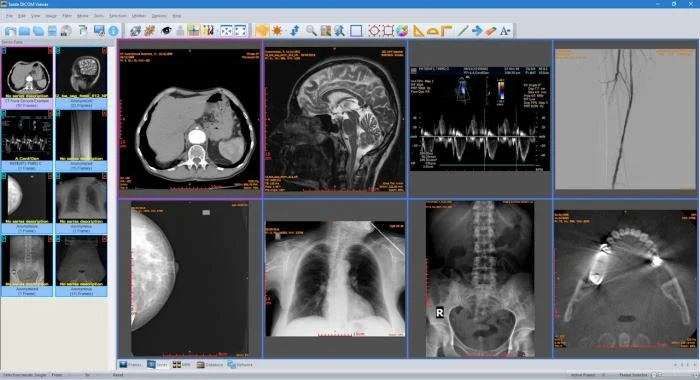

Популярные программы для просмотра DICOM-файлов (Windows, macOS, iOS, Android и Linux)

Видео-обзор лучших программ для просмотра DICOM-файлов